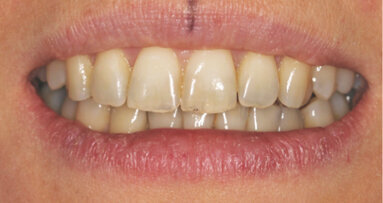

Diagnóza: I. třída Anglea, bialveolární protruze, stěsnání v horním i dolním zubním oblouku.

Byly vyhodnoceny fotografie enface, profil a estetika úsměvu. Pacientka požadovala zlepšení bialveolární protruze (obr. 1–8).